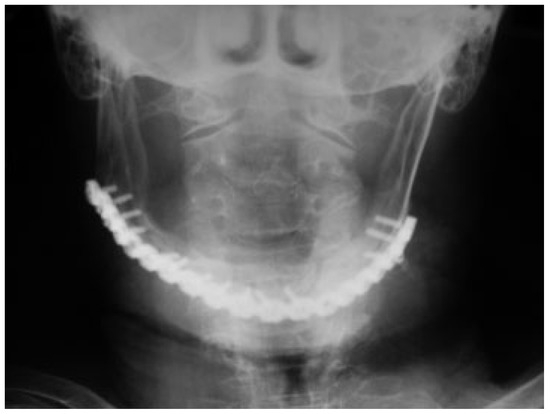

The patient recovered well in the postoperative period, which included use of diabetic and antihypertensive medications besides the usual postoperative medication. The immediate postoperative radiograph showed proper positioning of the segments (Figure 5), and the 2-month panoramic radiography demonstrated that reduction was maintained (Figure 6). The subcondylar fracture was treated with physiotherapy in the postoperative period [15]. The patient has 46 months of follow-up, with 34 mm of mouth opening without functional limitation. The osseous height at the site of the fracture was determined by reassessment [6,9,12], presenting 14 mm at its lowest point and rated as class II according to Luhr et al. [12] classification.

Figure 5. Segments properly positioned in the postoperative posteroanterior mandibular radiograph.